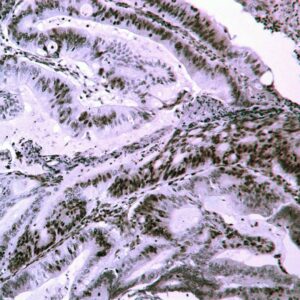

miRNA Probes

BioGenex has pioneered the development of miRNA research and diagnostics tools with leading-edge products. Currently, we offer over 240 ready-to-use (RTU) Super Sensitive™ Nucleic Acid (SSNA) miRNA ISH probes for accurate and early tumor diagnosis. These probes are sensitive enough to detect low-abundant miRNA(s) that are often required to identify biomarkers. They have a high melting temperature enabling stringent washes to remove non-specific binding. BioGenex miRNA probes are dual-end labeled with an anti-fluorophore to amplify the signal and yield clean and intense staining.